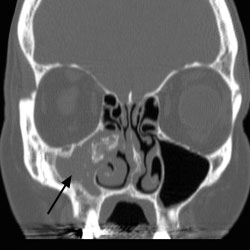

A fungus ball occurs when there is an overgrowth of fungal elements in the sinuses, particularly the maxillary and the sphenoid sinuses, where the fungus thrives in the warmth and humidity. Common molds such as…